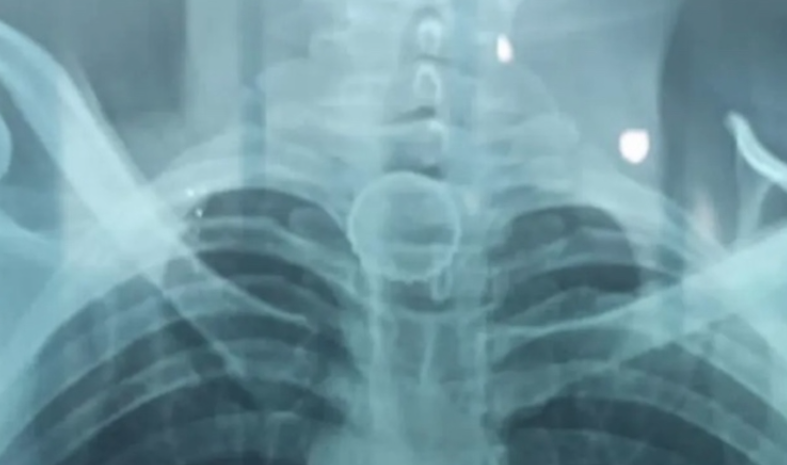

A tampa ficou presa no esôfago. Foto: Reprodução

A tampa foi parar no esôfago e o homem começou a passar muito mal, indo parar no hospital. Ele precisou ser transferido para o Hospital do Juruá, em Cruzeiro do Sul, no Acre, onde foi confirmada a posição do objeto em exames de imagem.